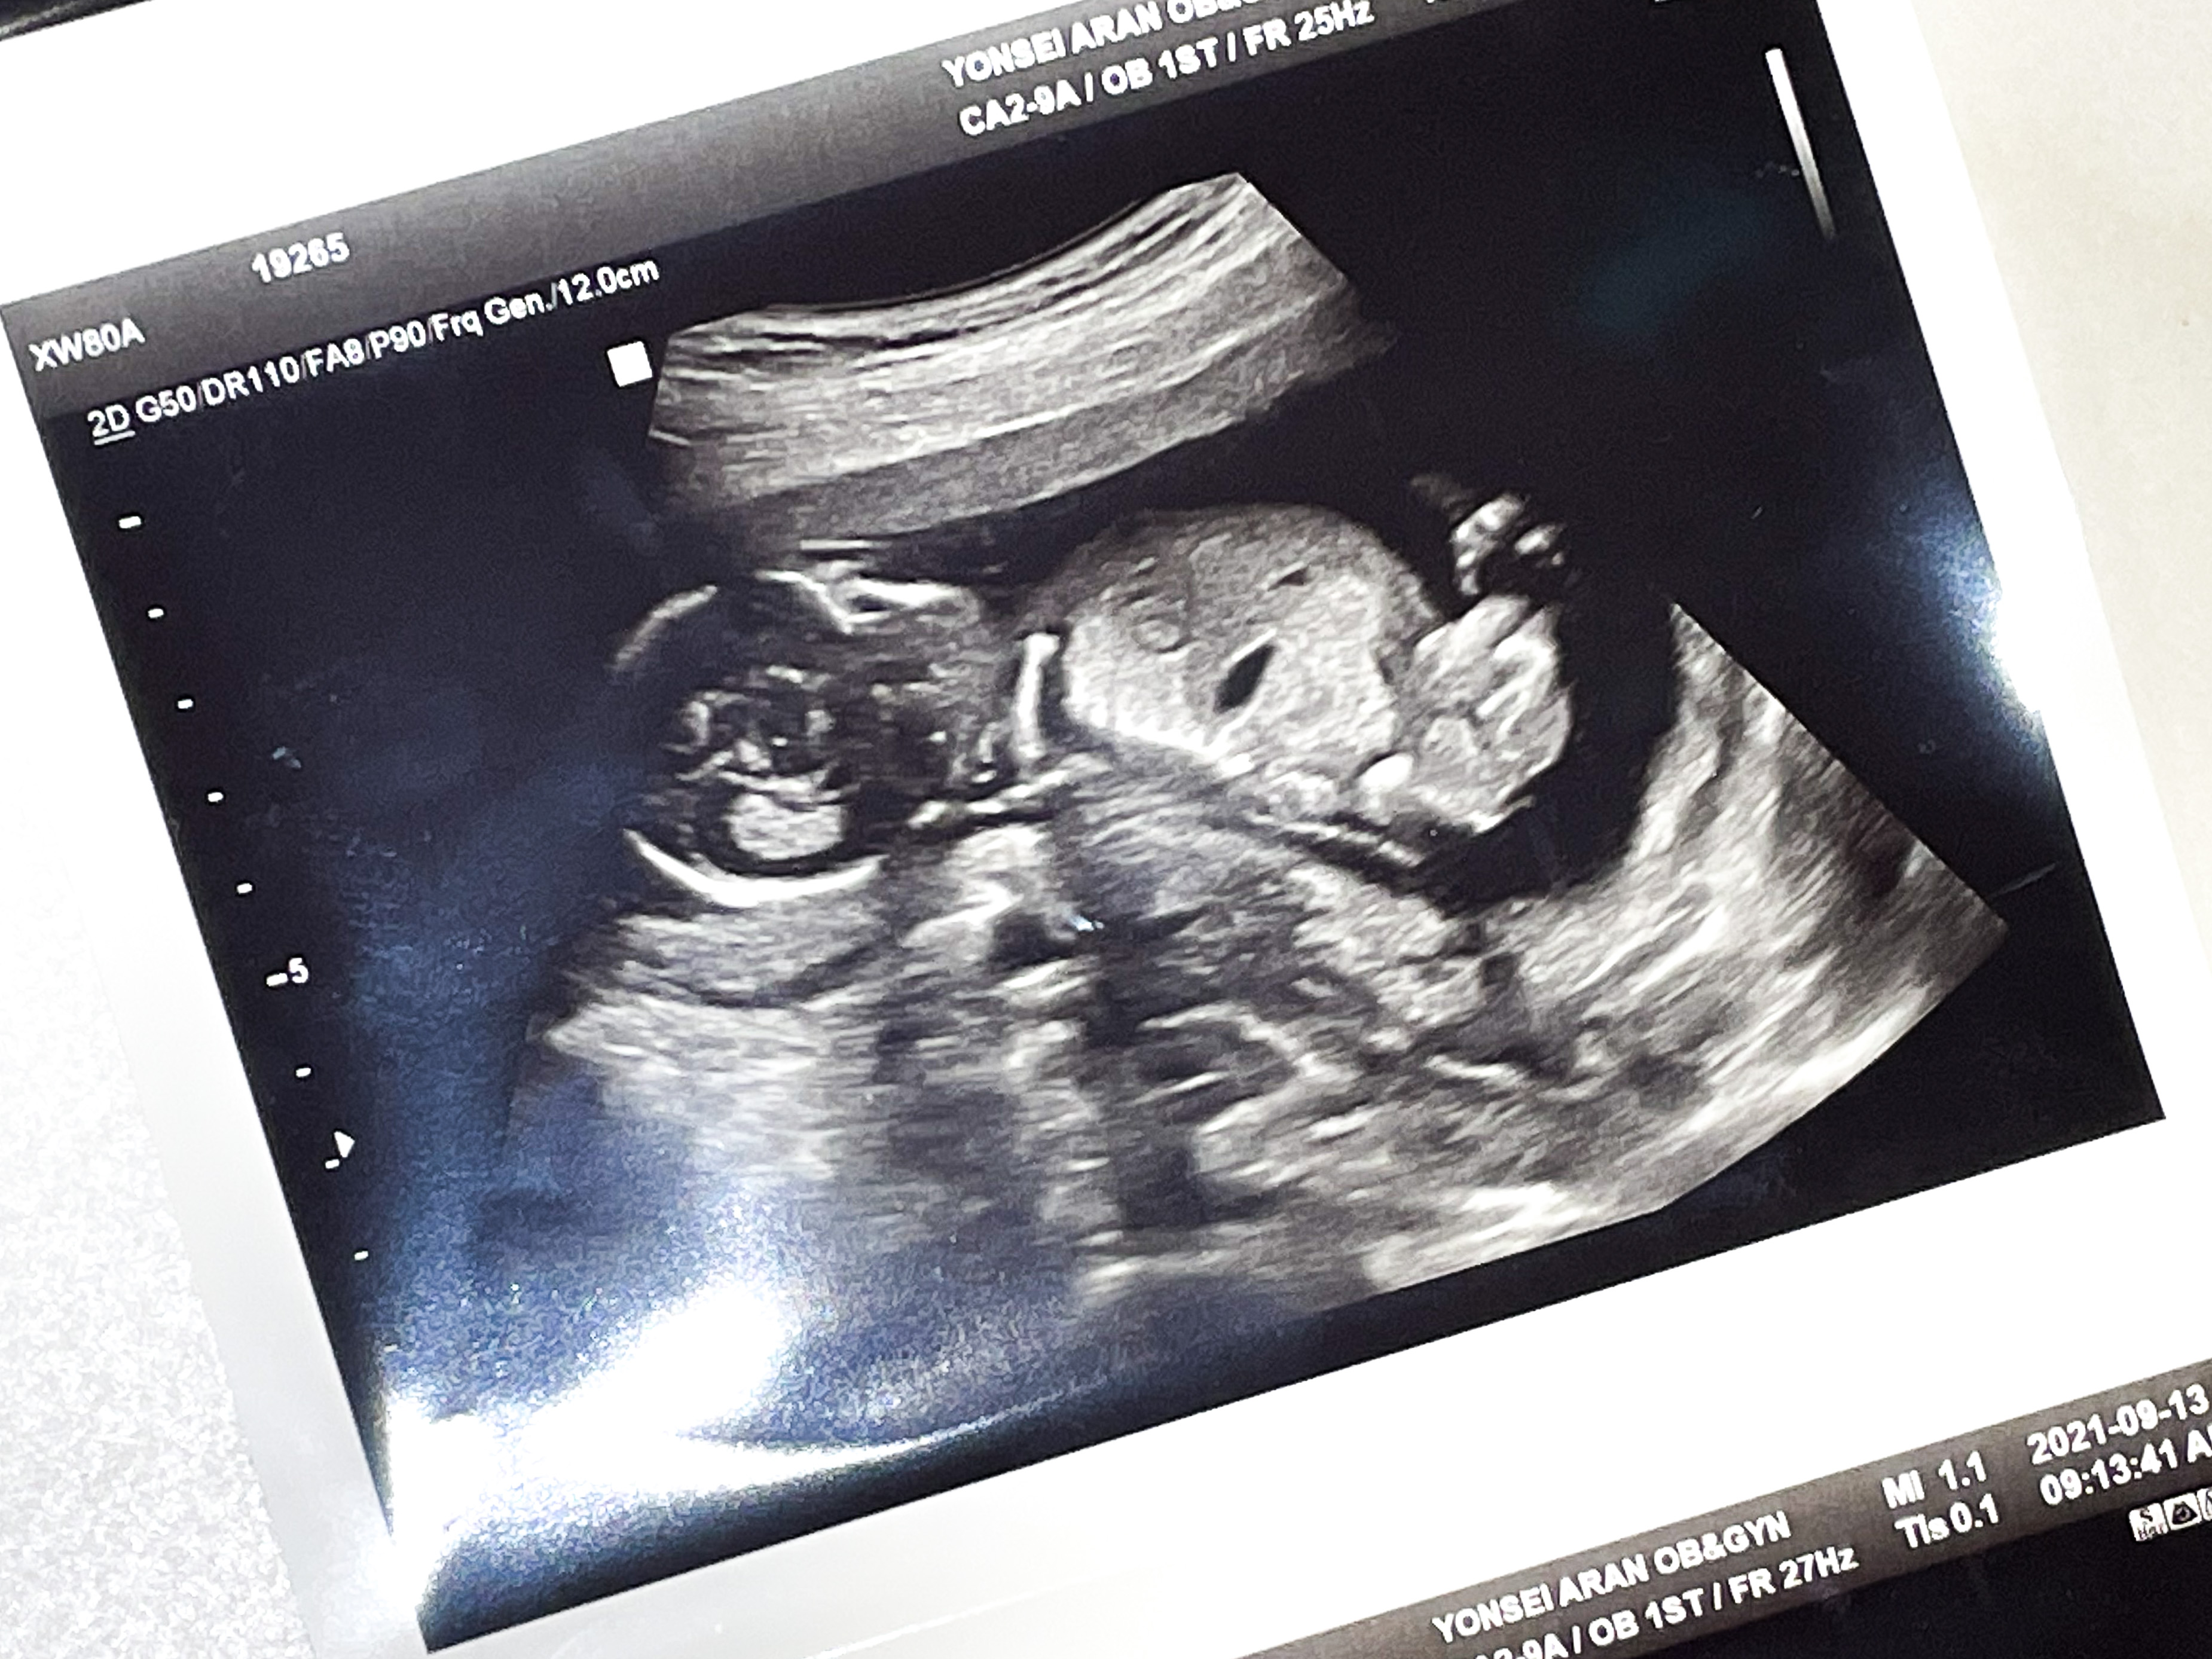

애기가 얼굴이 너무 잘보인다며 웃으셨다.

그와중에 머리는 역시 커졌고,